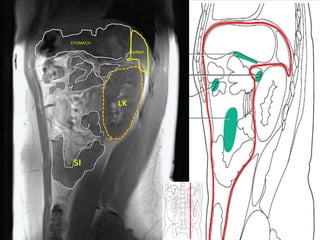

STOMACH

spleen

LK

SI